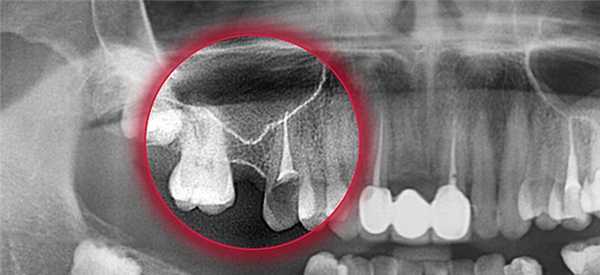

КТ придаточных пазух носа. Тотальное снижение пневматизации правой в/челюстной пазухи на фоне нарушения целостности и элевации ее дна (красная стрелка) вблизи корней 1-го моляра (синяя стрелка).

- Рентгенография околоносовых пазух. Показана при всех вариантах травм придаточных синусов носа. Позволяет визуализировать нарушение структурной целостности костей, образование костных обломков, их размеры и характер смещения, формирование гематом, заполнение полостей пазух кровью, наличие инородных тел. При недостаточной информативности рентгенограммы или подозрении на повреждение внутримозговых структур используется КТ и МРТ.

- Компьютерная и магнитно-резонансная томография. Проведение КТ лицевого скелета позволяет детализировать обнаруженные изменения, выявить минимальные скопления крови в пазухах и маленькие костные фрагменты, идентифицировать эмфизему орбиты и пневмоцефалию. МРТ головного мозга с контрастным усилением используется для диагностики сопутствующих повреждений головного мозга и разрывов регионарных кровеносных сосудов, поиска рентгенонегативных костных обломков.

- Рентгенологическое обследование. Рентгенография и КТ челюстей, рентгенография и КТ придаточных пазух носа. Определенную диагностическую ценность может представлять сцинтиграфия, термография.

- Рентгенография. Делают рентген пазуховой области. В случае появления перфорации на снимках будут видны затемненные участки - скопление в полости пазухи кровяного содержимого. Кроме того, можно также обнаружить частички корня зуба, материал, предназначенный для проведения пломбирования, или элементы импланта. Также рентген может проводиться с использованием контрастного вещества, которое вводят в полость через сформированный перфорационный свищ.

- Компьютерная томография. Благодаря данному методу диагностики можно выявить перфорацию и наличие инородного тела более точно.